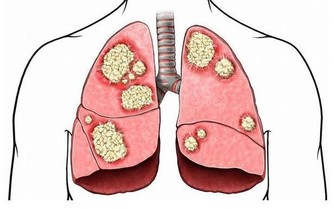

在患者的想像中,如果腎臟生了病,出現了腎炎,就應該小心使用,

而大量喝水,無疑會加重腎臟負擔,所以腎病患者喝水時都小心翼翼。